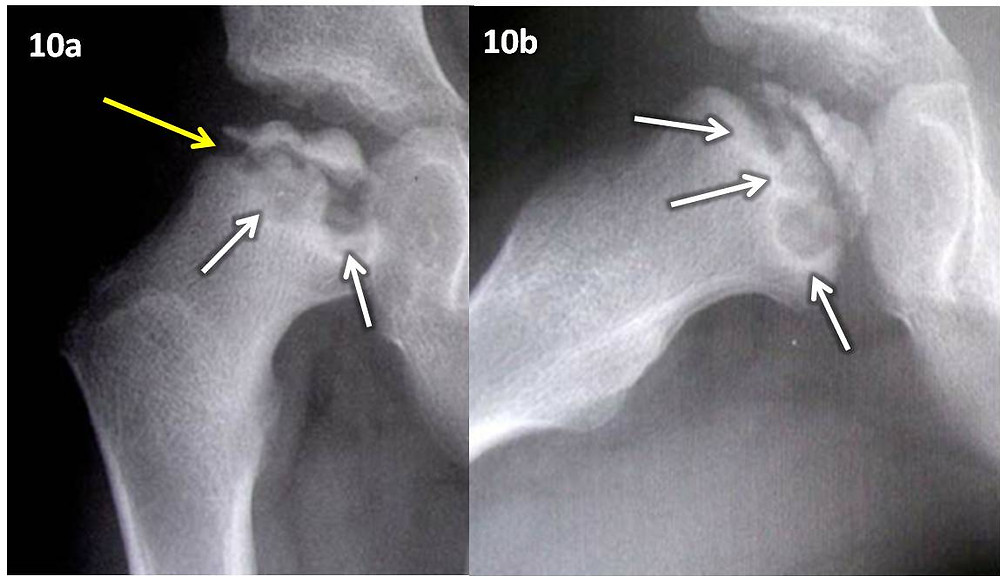

Abstract. Background: Legg-Calvé-Perthes Disease (LCPD) is a necrosis of the femoral head which affects the range of motion of the hips. Its incidence is variable, ranging from 0.4/100,000 to 29.0/ 100,000 children. Although LCPD was first described in the beginning of the past century, limited is known about its etiology.. Legg-Calve-Perthes disease (LCPD) occurs when blood supply to the ball of the thighbone in the hip (femoral head) is disrupted. Without an adequate blood supply, the bone cells die. Early symptoms may include limping; pain in the hip, thigh or knee; and reduced range of hip motion. Later in the disease course, there may be leg length.

It is a well-illustrated tome for the various surgical techniques presented. The chapter authors, all experts in LCPD, share their practical, innovative and comprehensive approach to this challenging condition. Legg-Calvé-Perthes Disease will be the definitive reference work on this condition for many years to come. Back to top.. La enfermedad de Legg-Calvé-Perthes es una afección de la cadera. En una cadera normal, la cabeza del fémur se apoya en la cavidad del hueso ilíaco. En la enfermedad de Legg-Calvé-Perthes, el suministro de sangre deja de llegar al hueso en esta articulación de la cadera. Por este motivo, el hueso comienza a descomponerse.